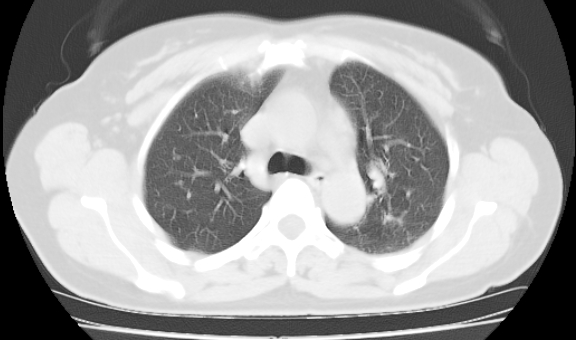

标题: CT25227:背部疼痛伴双侧胸壁痛2月,食欲差。 [打印本页]

标题: CT25227:背部疼痛伴双侧胸壁痛2月,食欲差。

肺结核并胸椎结核?请各位高手指教。

用椎体的条件来扫胸椎呀!考虑1左侧胸膜小结节形成2椎体结核并冷脓肿形成

左肺结核灶,胸椎结核并冷脓肿。

左肺结核灶,胸椎结核并冷脓肿